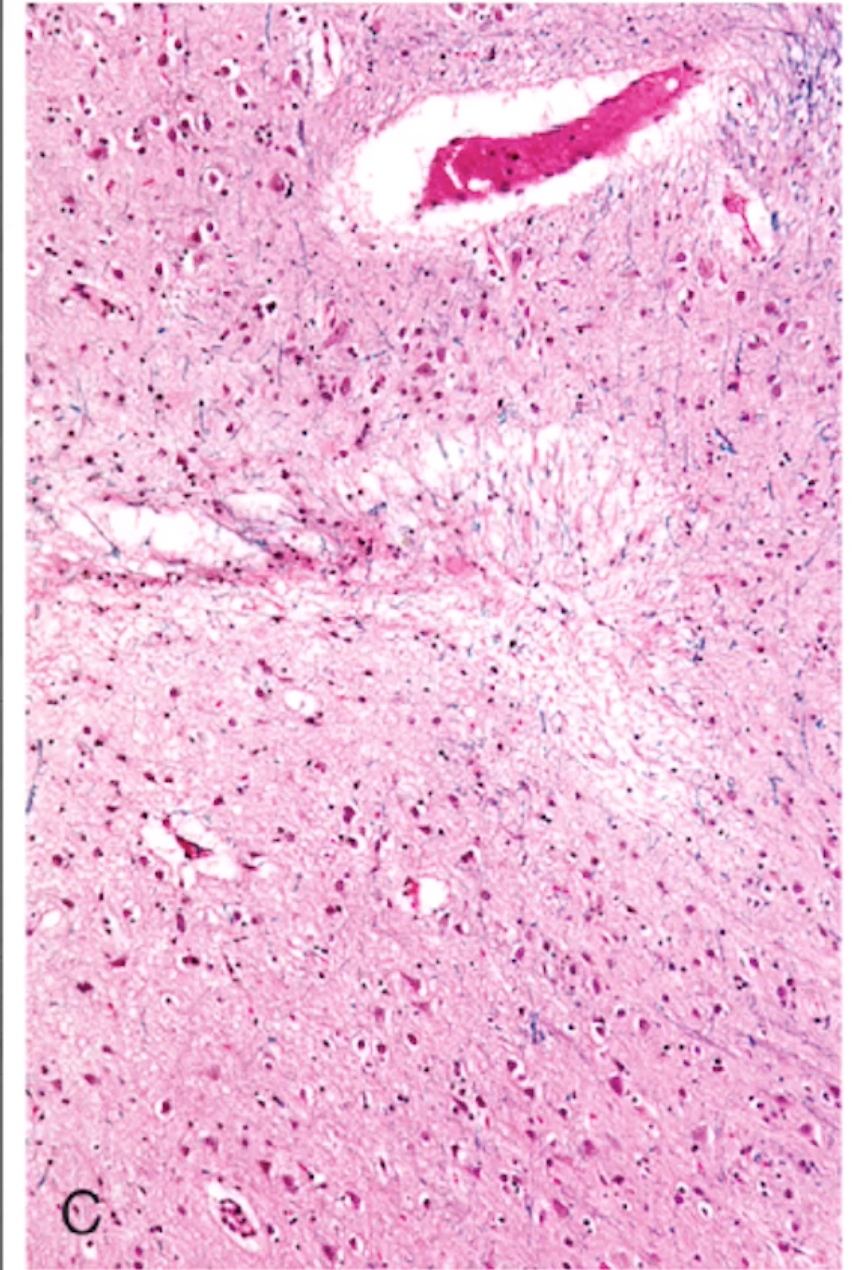

Focal Cerebral Ischemia